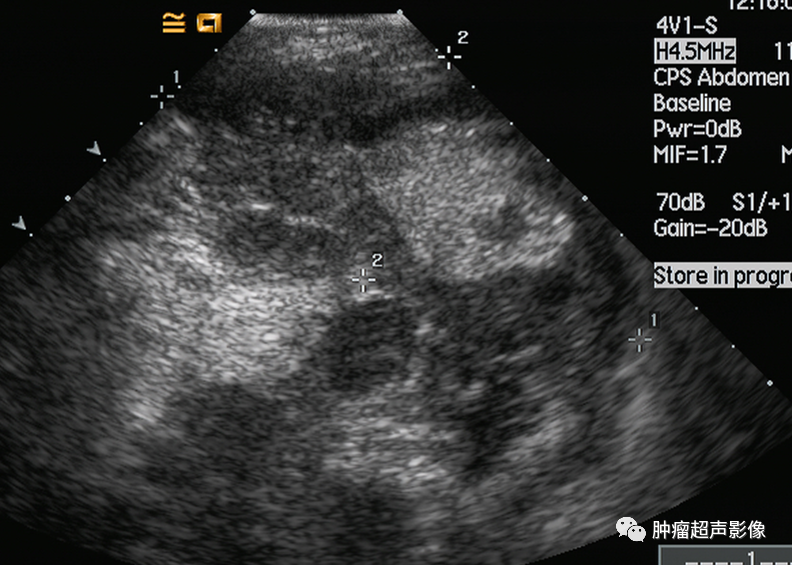

胃淋巴瘤:矛盾现象:肿块虽大,但是并未明显向外侵犯,增厚的胃壁厚薄相对均匀,黏膜及浆膜反射界面比较光整,胃外形规则(病例来自云南胃肠超声群会诊病例)

皮革胃:外形不规则,明显侵犯周边组织,胃壁厚薄不均。